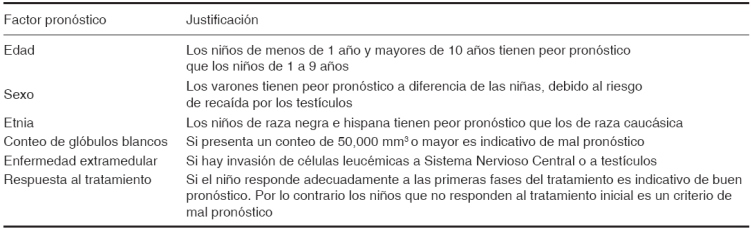

El diagnóstico médico de la leucemia se basa en la sintomatología característica y en los estudios de laboratorio que se le indiquen al paciente (Cuadro II). Generalmente para corroborar el diagnóstico se indica un aspirado de médula ósea para valorar si existe o no invasión de blastos, si existe una blastosis medular que supere el 30% de la totalidad celular se podrá emitir dicho diagnóstico. Además de los conteos celulares de la biometría hemática que se caracterizan por tener un conteo elevado de leucocitos (mayor de 50,000 mm3) y la presencia de blastos reportados en la misma, y en consecuencia una disminución importante en el conteo de las plaquetas, neutrófilos, hemoglobina, eritrocitos.

La citogenética es muy importante para determinar el pronóstico de la leucemia. Cuando en el estudio citogenético se observan células con un mayor número de cromosomas (denominadas hiperdiploides) los pacientes tienen mayores posibilidades de cura, a diferencia de los pacientes que tienen menor cantidad de cromosomas (hipodiploides) que generalmente tienen peor pronóstico. La presencia del llamado cromosoma Filadelfia es un factor que determina mal pronóstico para la enfermedad también.4,5,7

Sin embargo, además de la citogenética existen otros factores que condicionan el pronóstico de la leucemia (Cuadro III).